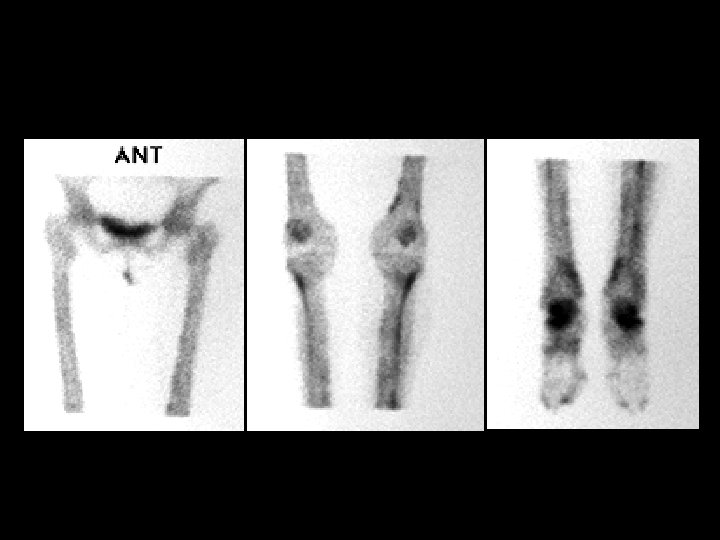

Engelmann’s disease • Findings: – Increased diaphyseal activity and expansion of the lower extremities – Radiographs show marked of the diaphyseal corticies affecting both periosteal and endosteal surfaces – Progressive diaphyseal dysplasia; autosomal dominant, variable expression • ddx: – Osteopetrosis – Melorhostosis – Hyperphosphatasia – Fibrous dysplasia